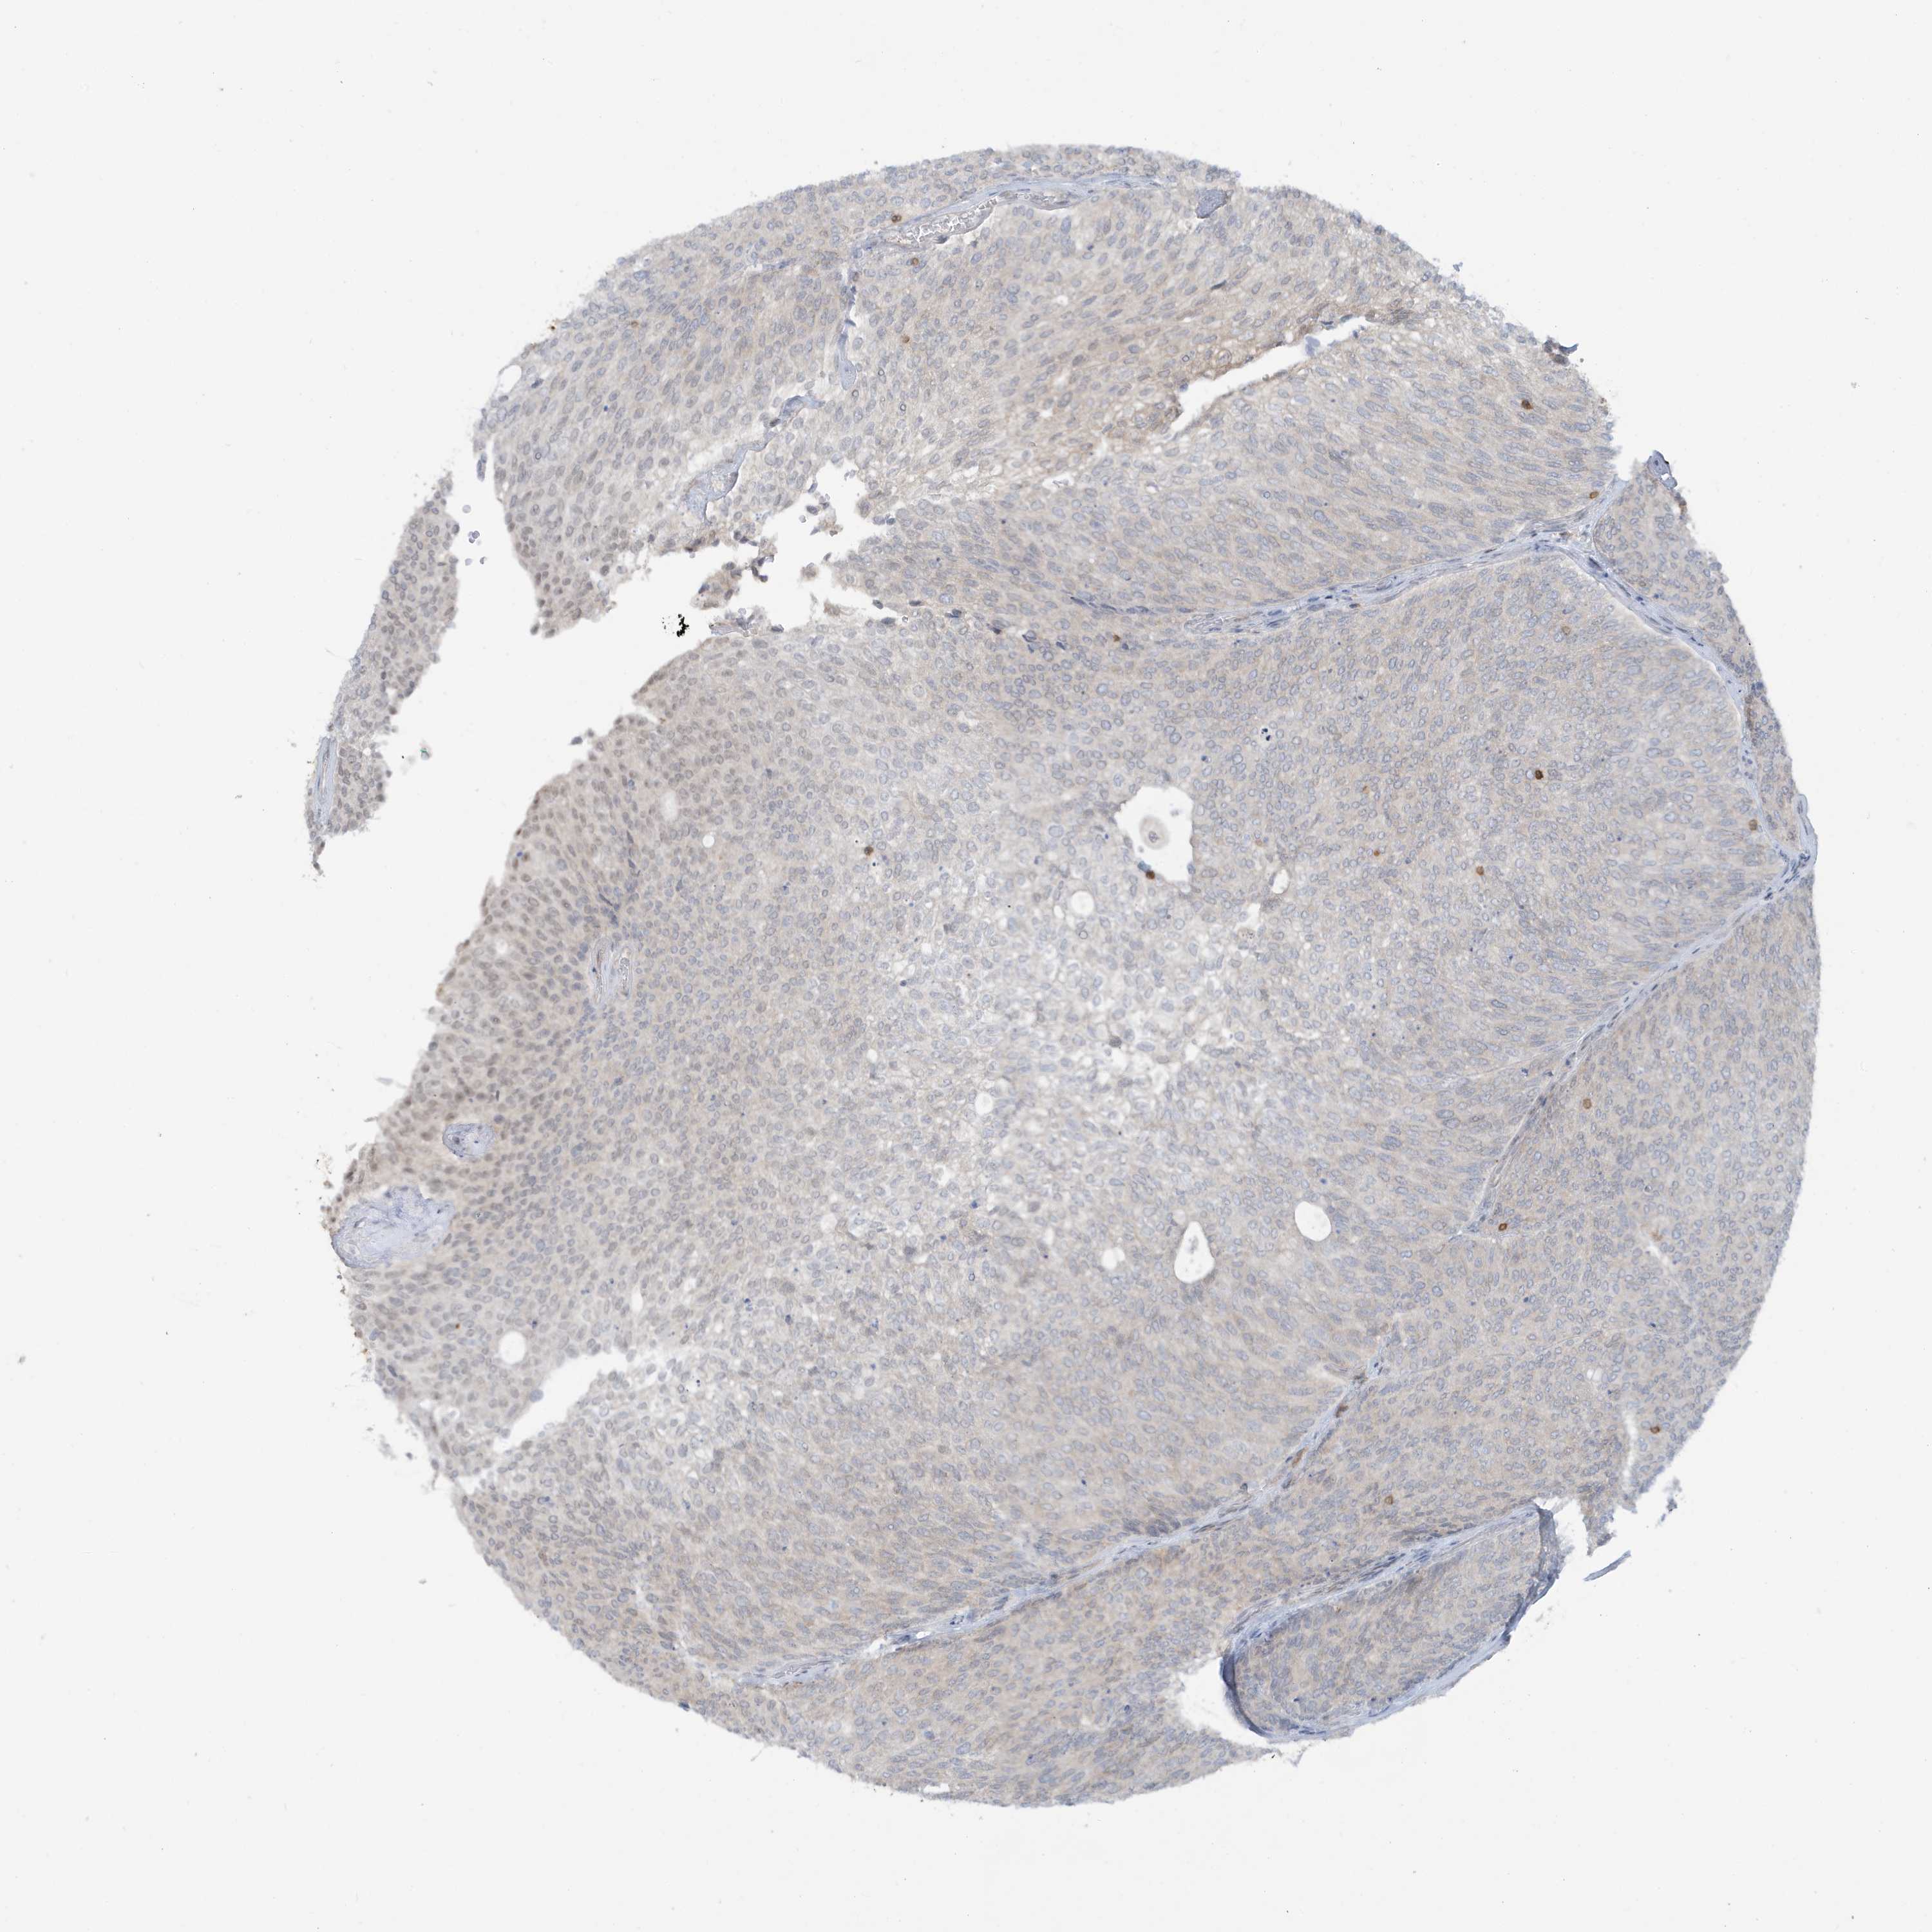

UROTHELIAL CANCER - Protein expressioni

A mouse-over function shows sample information and annotation data. Click on an image to view it in a full screen mode. Samples can be filtered based on level of antibody staining by selecting one or several of the following categories: high, medium, low and not detected. The assay and annotation is described here.

Antibody stainingi

Antibody staining in the annotated cell types in the current human tissue is reported as not detected, low, medium, or high, based on conventional immunohistochemistry profiling in selected tissues. This score is based on the combination of the staining intensity and fraction of stained cells.

Each image is clickable and will lead to virtual microscopy that enables deeper exploration of all samples and also displays staining intensity scores, fraction scores and subcellular localization as well as patient and tissue information for each sample.

Antibody HPA036141

Staining

High

Medium

Low

Not detected

Intensity

Strong

Moderate

Weak

Negative

Quantity

>75%

75%-25%

<25%

None

Location

Nuclear

Cytoplasmic/membranous

Cytoplasmic/membranous,nuclear

Urothelial carcinoma, Low grade

Urothelial carcinoma, High grade